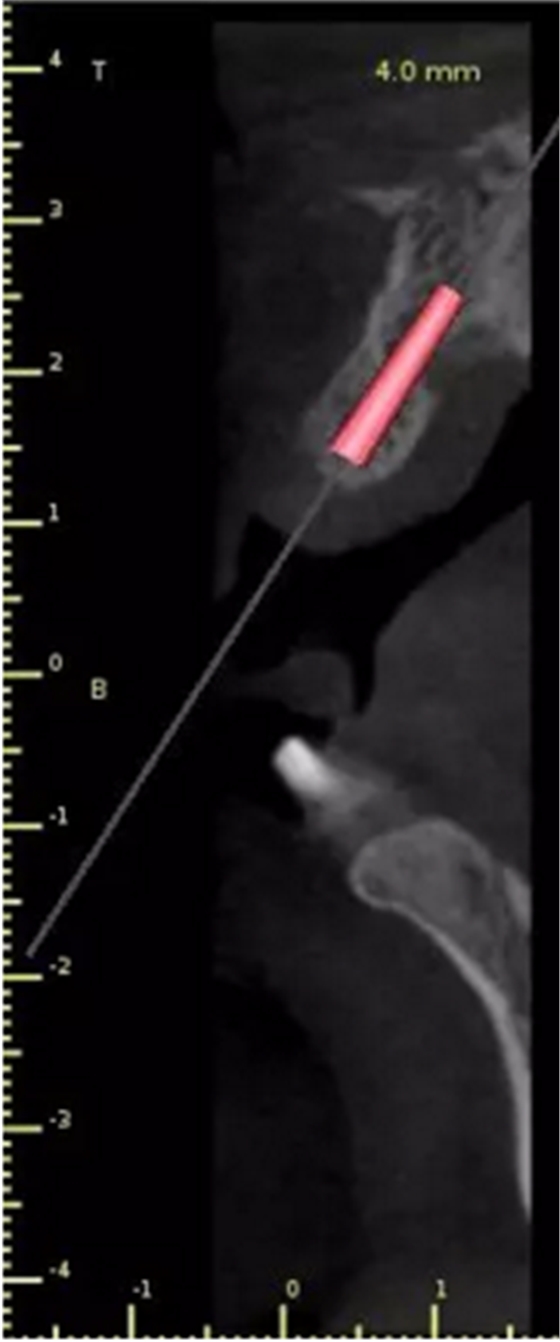

1.術(shù)前CT

2.術(shù)前植體設(shè)計(jì)